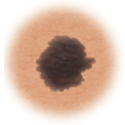

Atypical moles (dysplastic nevi)

Larger than normal moles (more than a half inch across), atypical moles are not always round. They can be tan to dark brown, on a pink background. These types of moles may occur anywhere on the body.

Treatment may include removal of any atypical mole that changes in color, shape, or diameter. Also, people who have them should avoid sun exposure, since sunlight may accelerate changes. People with atypical moles should see a doctor for any changes that may indicate skin cancer.